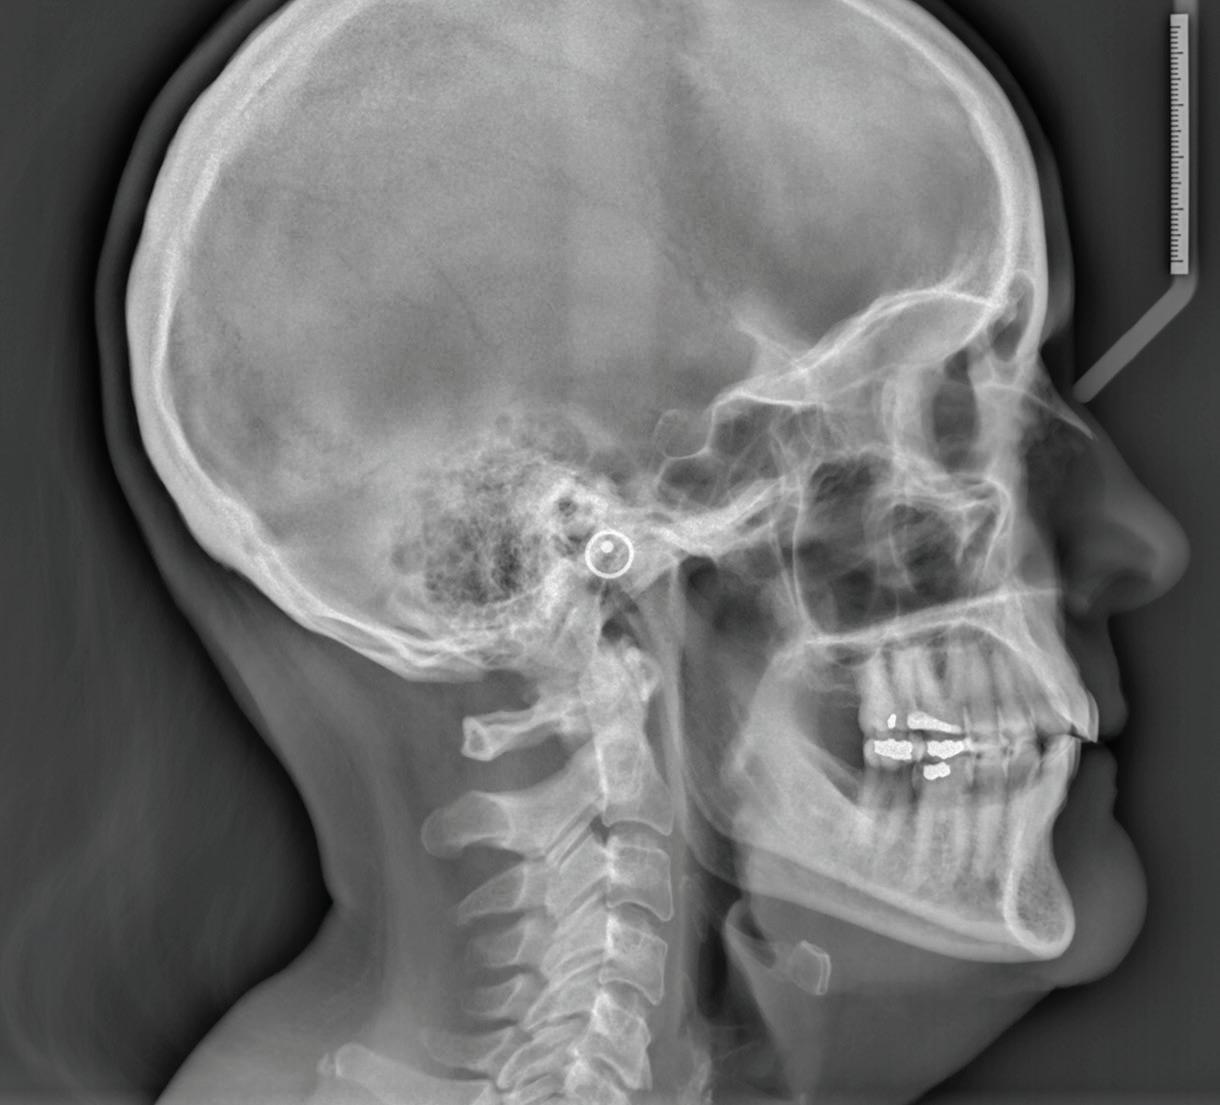

Clear aligner therapy and symptoms of temporomandibular disorders: a case report

Lina Sharab

Bushra Butul

Aqib Shafi

Jeffrey P. Okeson

SELF-INSTRUCTION EXERCISE GD538, 2 CE CREDITS, P. 53